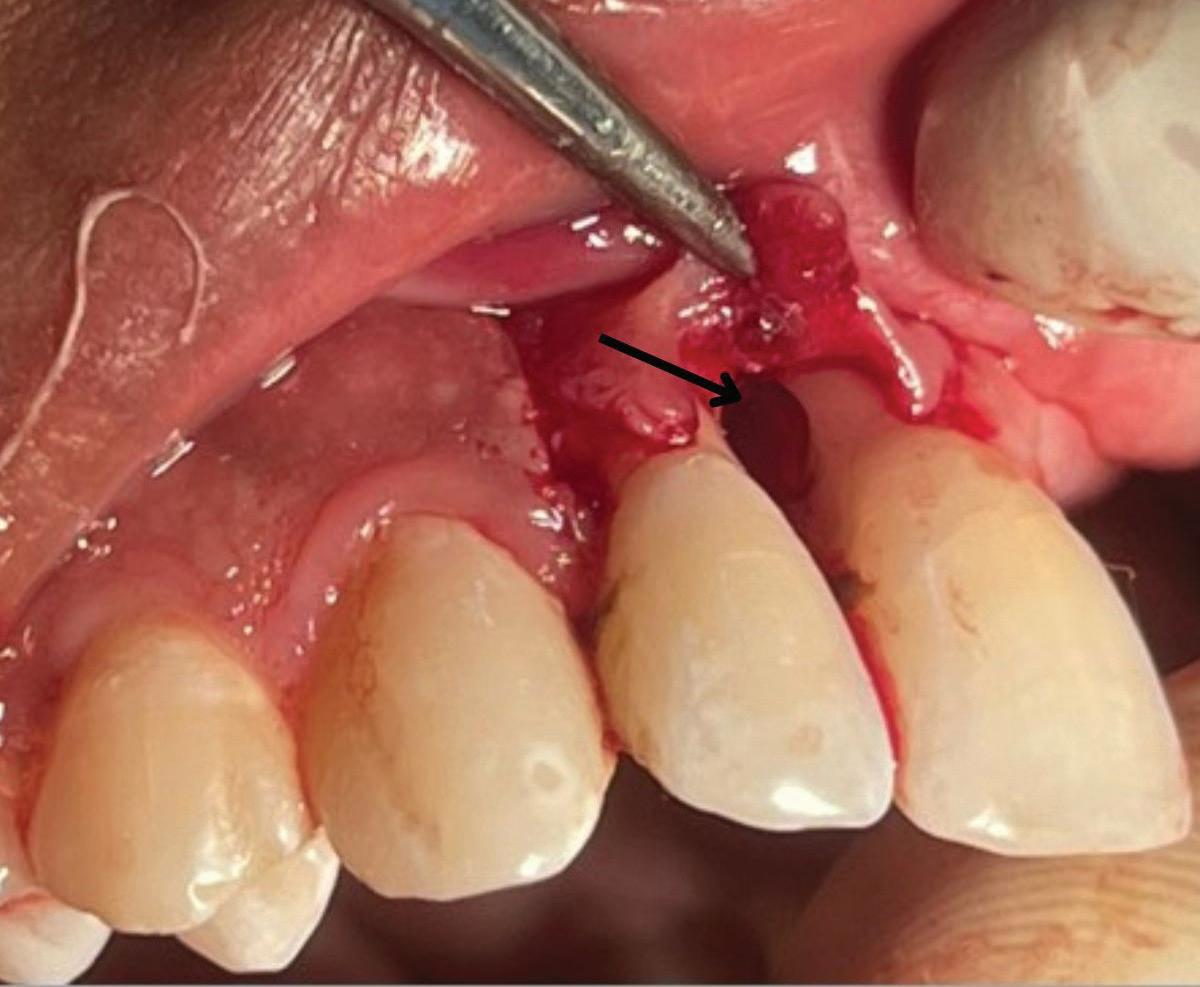

When endodontic irrigants or materials are extruded in teeth with fenestrations, they not only exit beyond the apex but also may enter directly into soft tissue or mucosal spaces, dramatically increasing the risk of postoperative swelling, pain, and delayed healing. In a recent retrospective case series investigating sodium hypochlorite extrusion injuries, fenestrations were identified in all 26 reported cases (Fig 3).23

Fig 3. Sodium hypochlorite was extruded through a perforation that occurred during endodontic treatment of the maxillary left canine, causing immediate bruising, swelling, and pain.